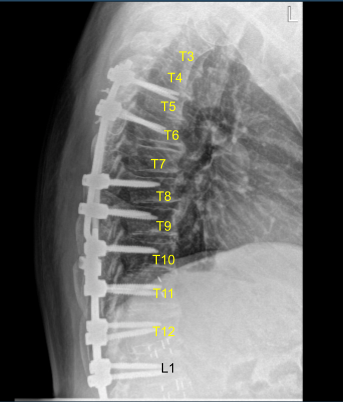

The physical examination showed tenderness of the paraspinal region at L5 on the left and right side. Fractured left-sided thoracic Z-rod with pseudoarthrosis and laterally placed proximal pedicle screw. Ct study conducted prior to the surgery supported the preoperative diagnosis of thoracic pseudoarthrosis.

Sagittal View of Preoperative CT-Scan